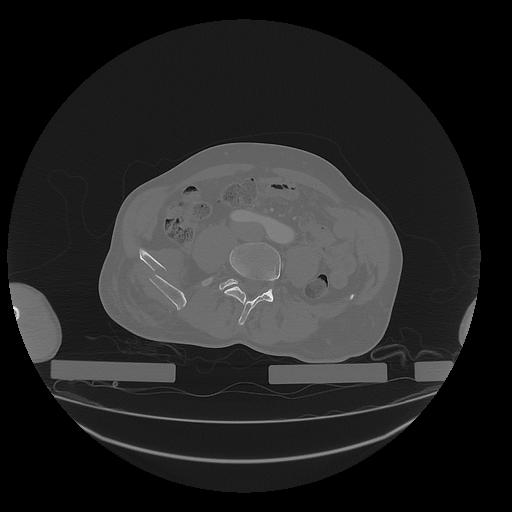

31 PULMON,CE,Vol,1.0,PULMON,,